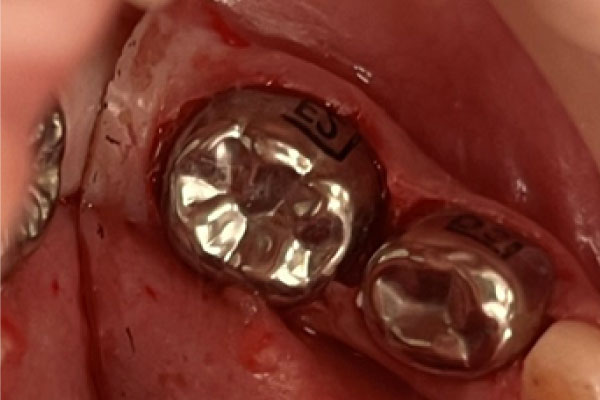

- Доктор владеет передовыми технологиями в лечении и восстановлении как молочных, так и постоянных зубов, обеспечивая эффективное и безопасное лечение;

- 2024 - APPD - "Восстановление молочных зубов коронками"